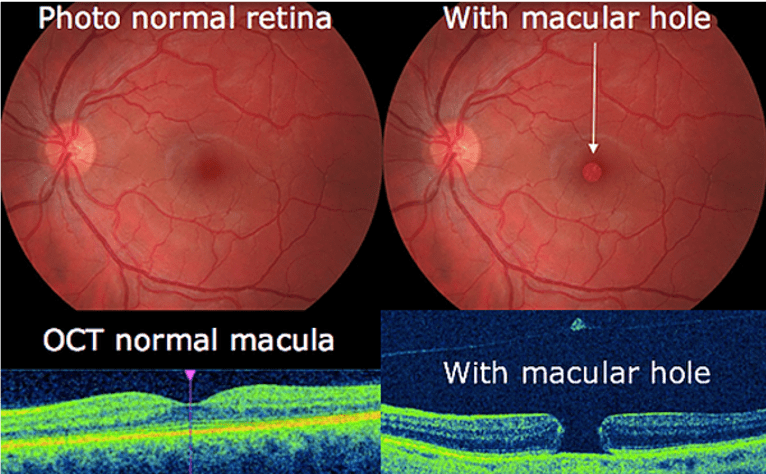

What is a macular hole?

A macular hole is a tear or opening in the macular, the central part of the retina. As the hole forms, the central vision becomes blurry, wavy or distorted. If the hole extends, the central vision can develop a dark spot or blind spot.

What causes a macular hole?

Age is the most common cause. Macular holes are more common as we become older. The vitreous gel in our eye shrinks and this causes traction or pulling on the retina and over time can cause a hole to form.

What is the treatment for macular holes?

After macular hole surgery:

- You will need to keep a face down position for most of the day for a week or more. This is so that the gas bubble will float up against the macular and stay in position for the macular hole to close properly.

- Air travel, mountain climbing and diving should be avoided as this may cause the gas bubble to expand resulting in eye pressure problems.

- Vision will be blur immediately after surgery due to the gas bubble. Over time, vision will improve as the gas bubble reduces and healing of the macular hole occurs. The amount of vision you get back also depends on the size of the hole and the length of time the hole was present before surgery.